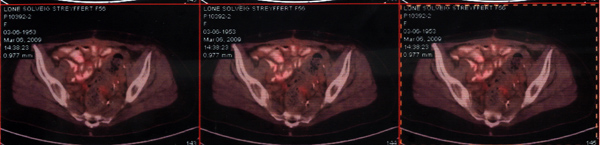

2013年10月15日来院复查,PET-CT显示腹腔内无活性癌肿存在证据。

Sara小姐治疗后CT